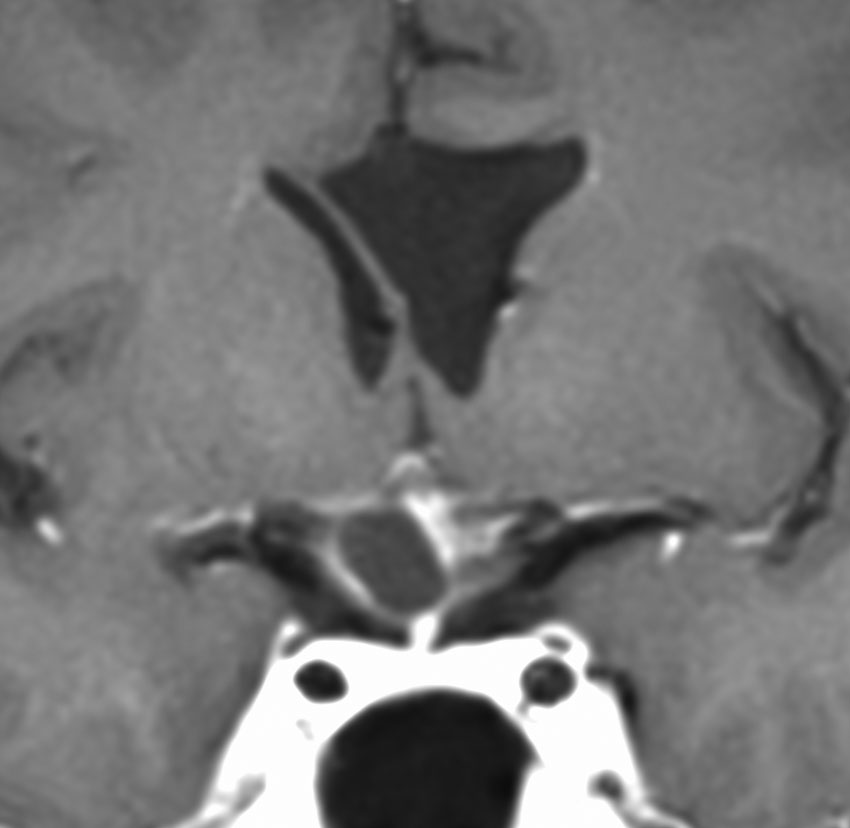

視神経への圧迫はとれたので,今度は腫瘍の本体を摘出しなければならないのですが,トルコ鞍上部に大きな骨化(黄色の矢印)があります。骨化は15mmくらいの大きさがありました。この大きな骨化は砕くことができずに,周囲を全部剥離して一塊にして引きずり出しました。後交通動脈の下側から引っ張りだしたのですが,かなり危険な手術操作でした。結果的には,下垂体柄を温存できて腫瘍を全摘出しました